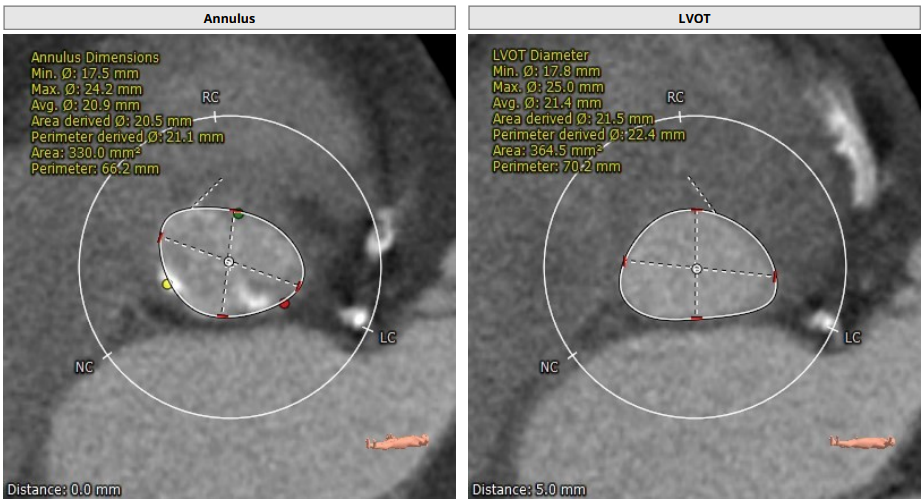

瓣环平均直径:21.1 mm,左室流出道平均直径:22.4mm。

升主动脉(未见)明显扩张,心脏角度:50°。

左冠高度:10.6mm,右冠高度:14.5mm。

钙化积分:61.2mm³,轻度钙化。